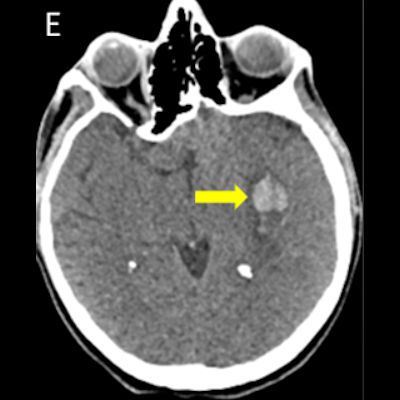

- Kontrastsız BT görüntülemede (E) bu düzeyde intraparankimal kanama ile uyumlu hiperdens alan gözleniyor (ok).